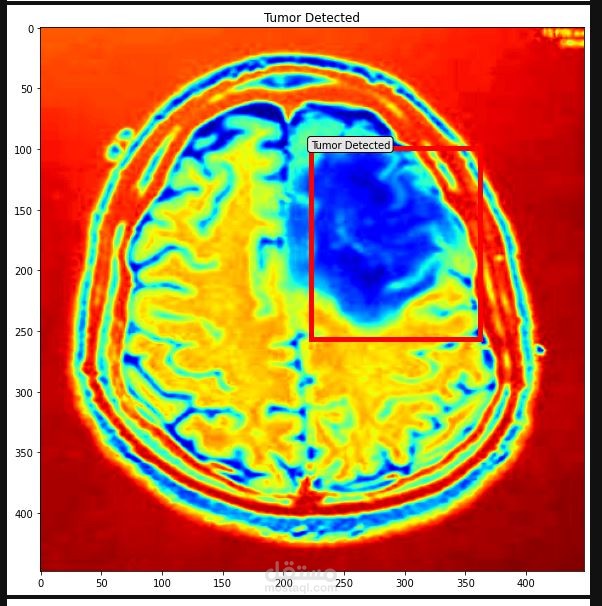

The goal of the project was to build a system that could accurately classify brain tumors as benign or malignant, as well as detect the location of the tumors within an MRI scan. To achieve this, I used PyTorch to train a deep convolutional neural network (CNN) on a large dataset of MRI scans annotated with tumor labels and bounding boxes.

I also used the YOLO (You Only Look Once) object detection algorithm to enhance the accuracy of the tumor detection component of the system. YOLO is a fast and efficient algorithm that is well-suited for real-time object detection tasks.

Overall, the project was a success and the system was able to achieve high levels of accuracy in both tumor classification and detection. The use of deep learning and advanced techniques like PyTorch and YOLO allowed me to build a powerful and effective solution to this important medical problem.